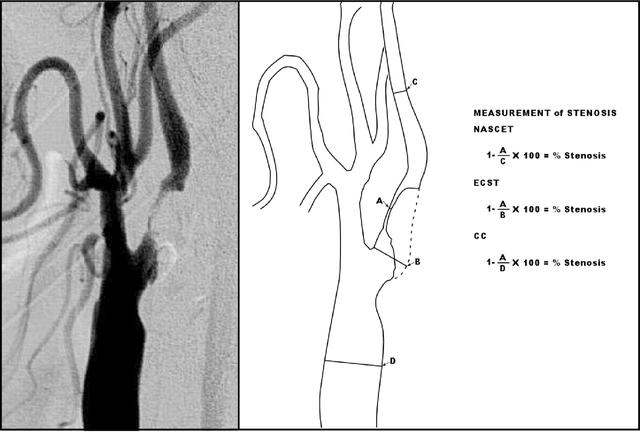

检查颈动脉,身体检查可以听诊颈部血管有没有杂音(轻度的狭窄不一定有杂音),辅诊检查初筛是颈动脉超声,无创伤,可以重复,但一般对狭窄病变有些放大(就是说看起来可能比真实的狭窄要严重些);进一步检查可以做颈部血管的磁共振血管造影或者CT颈动脉造影,这两种检查也属于无创,但是需要注射造影剂的;再就是直接插入导管做颈动脉造影。

颈动脉有狭窄怎么办?严重的当然要开通。一般来说,如果有脑缺血发作的症状或者有了脑梗死,磁共振或者CT颈动脉造影显示70%或以上的狭窄、或者直接的血管造影狭窄在50%或以上,就要手术开通血管了(当然还有其他一些指证)。最经典的手术方法就是前面说过的颈动脉内膜剥脱(切除)术,现在还有微创的颈动脉支架植入术。各种手术方法都是有各自的适应证的。